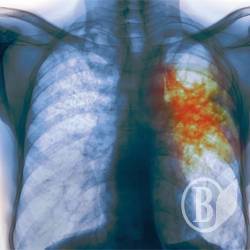

В детсаде Чернигова воспитательница оказалась больной открытой формой туберкулеза

Одна из воспитательниц черниговского детсада №22 оказалась больной открытой формой туберкулеза.

«А в мае она оказалась больной открытой формой туберкулеза, хотя эта стадия длится от 6 до 10 месяцев. Врачи же на собрании заверяли, что она только что заболела», - пишет Виктория Пискун.